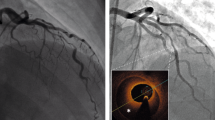

A 65 years old female patient with systolic hypertension, dyslipidemia, history of transient ischemic attack and diagnosis of Patent Foramen Ovale (PFO) subjected to a percutaneous closure procedure with Amplatzer device 1 year ago, was referred to our Hospital for No-ST segment elevation myocardial infarction (NSTEMI). The electrocardiogram ( ECG) showed diffuse repolarization abnormalities (Fig. 7.1), and the peak of high sensible (HS) Troponine T was 0.168 ng/mL. Trans-thoracic echocardiogram revealed a slightly hypertrophic left ventricle (LV), with normal volumes and preserved global and regional function, and Amplatzer device localized in the atrial septum. The contrast echocardiography did not show passage of microbubbles from the right to the left atrium both at rest and after the Valsalva maneuver, rulling out the hypothesis of acute myocardial infarction (AMI) caused by embolization. Coronary angiography did not point out the presence of significant coronary stenosis, while intra-coronary ergonovine administration (up to 50 μg) caused diffuse ST-segment depression at ECG and symptoms, in absence of epicardic coronary spasm (Fig. 7.2, panel A and B). For this reason, the diagnosis of MI and non-obstructive coronary arteries ( MINOCA) due to coronary microvascular spasm (CMS) was done. The medical therapy was optimized with the add of calcium blockers and the patient was discharged without symptoms 7 day after. She remained asymptomatic until 4 years later, when she was admitted at our Hospital for sinus nodal disease and underwent to the procedure of pacemaker implantation.